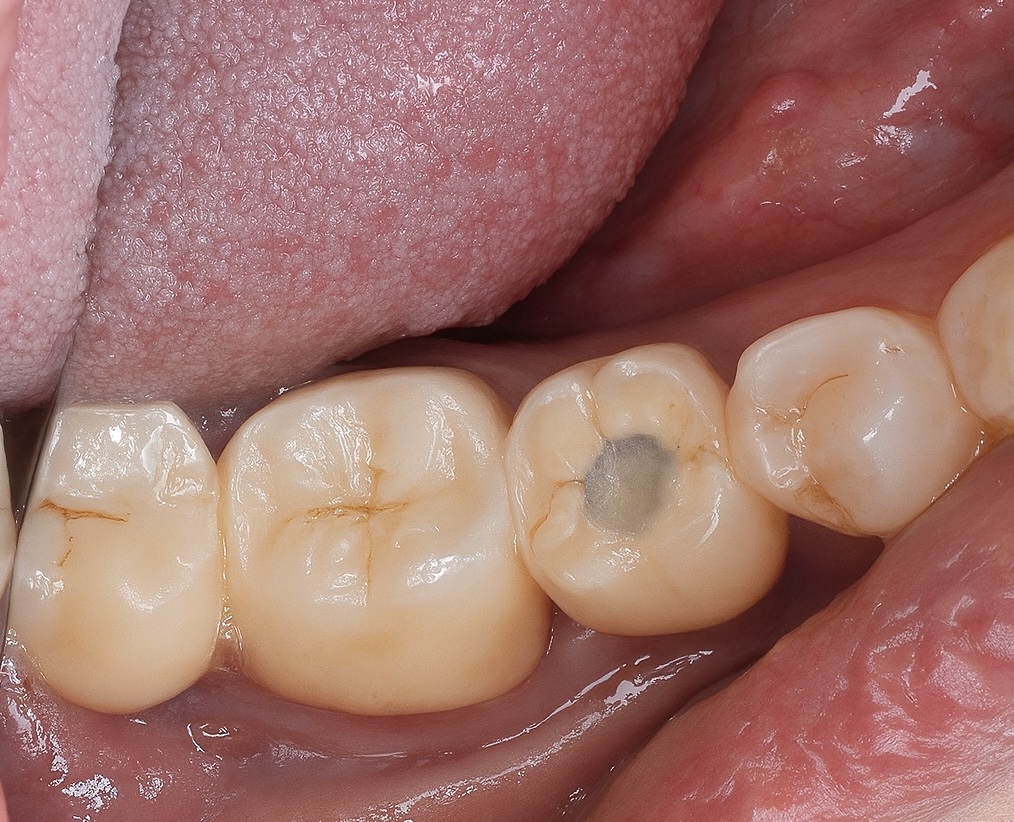

6️⃣ Post-Operative Evaluation

Radiographic follow-up showed precise osseointegration, proper emergence profile, and marginal bone stability (Fig 6). The final prosthesis integrated seamlessly with natural dentition and provided excellent function and esthetics (Fig 7).